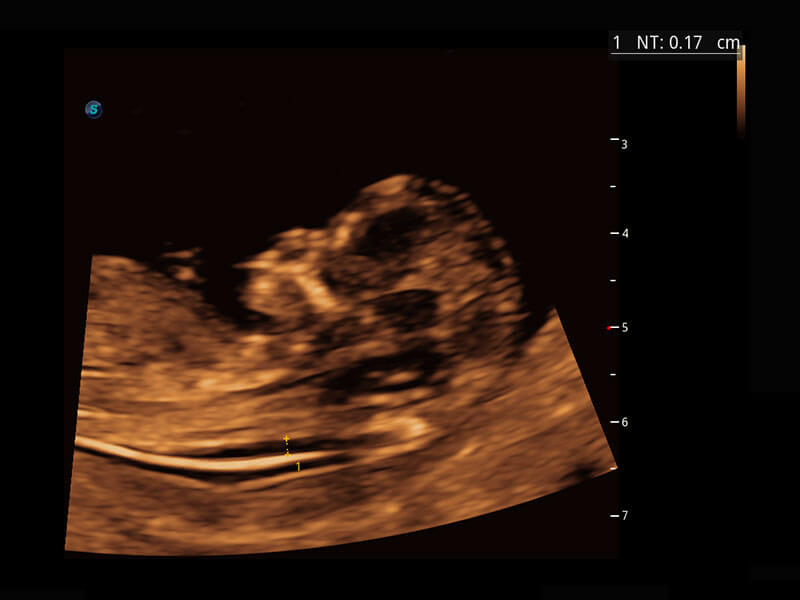

P60在胎儿早孕期超声筛查中为您带来优异的图像质量。

早孕-胎心

P60提供简单易学易用的高端诊断工具,为您中晚孕筛查提供快速清晰的解剖信息。